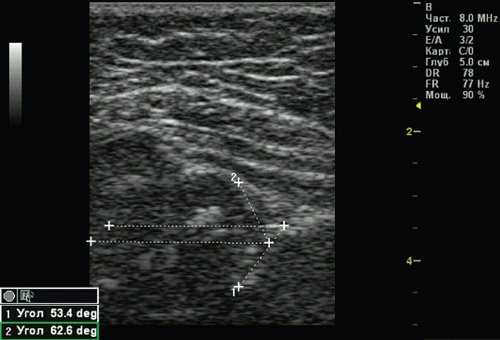

Рис. 4. Тазобедренный сустав тип 2б.

1 - угол α=53,4°;

2 - угол β=62,6°.